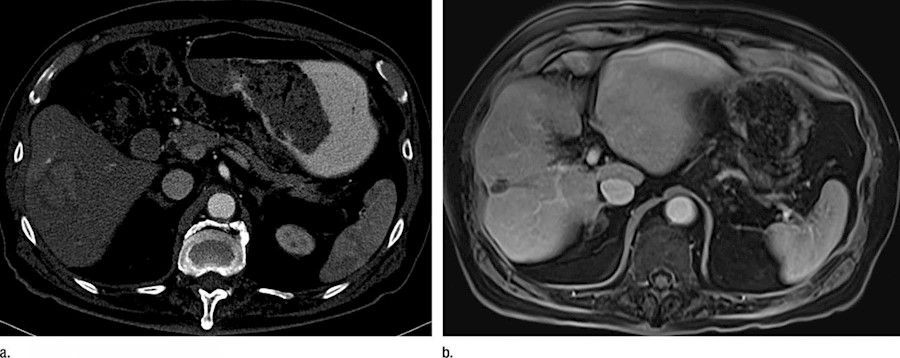

Un primer ensayo clínico en humanos demuestra una mejora en el tratamiento con radiación del cáncer de hígado

Una nueva investigación ha demostrado, a través del primer ensayo clínico en humanos, que el actual tratamiento del cáncer del hígado mediante radioterapia dirigida administrada con la ayuda de perlas de vidrio que emiten radiación se puede aumentar al infundir microburbujas (pequeñas burbujas de gas rodeadas por una capa de lípidos) en el hígado y hacer estallar esas burbujas por ultrasonido, según publican los investigadores en la revista `Radiology`.

Alrededor del 15-25% de los pacientes con enfermedad avanzada se les recomienda un tratamiento llamado radioembolización transarterial, mediante el cual se insertan perlas de vidrio radiactivo en los vasos sanguíneos del hígado, y la radiación emitida proporciona una dosis terapéutica al tumor, destruyéndolo.

Sin embargo, la medida en que la radiación puede penetrar en el tejido hepático es limitada y la respuesta del tumor depende en gran medida de la distancia a las perlas radiactivas. Al combinar microburbujas con TARE, el enfoque sinérgico reduce la dosis de radiación necesaria para destruir los vasos sanguíneos del tumor y aumenta la eficacia del tratamiento.

El estudio piloto incluyó a 28 pacientes que fueron asignados aleatoriamente a dos grupos de tratamiento: radioembolización transarterial sola (TARE) o radioembolización y destrucción de microburbujas activada por ultrasonido (TARE + UTMD).

Los investigadores observaron 10 tumores en el grupo TARE solo y 15 tumores en el grupo TARE + UTMD, y evaluaron la respuesta tumoral a cada tratamiento. El 93% de los tumores mostró una respuesta parcial o completa al enfoque TARE + UTMD, mientras que solo el 50% mostró una respuesta en el grupo de TARE solo.